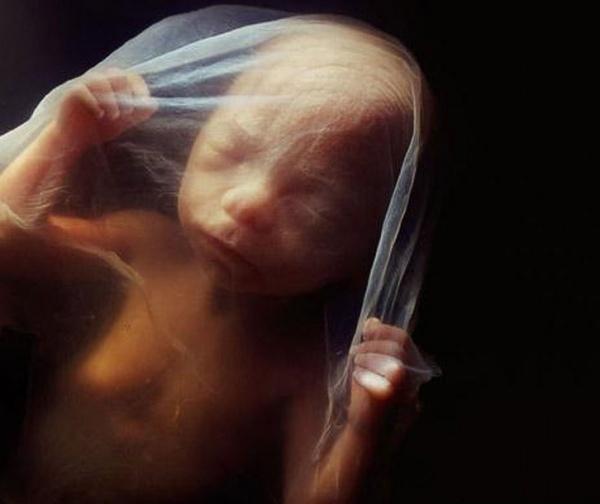

8 εβδομάδων

10 εβδομάδων. Τα βλέφαρα είναι ήδη λίγο ανοιγμένα. Σε μερικές ημέρες θα είναι τελείως σχηματισμένα

Στις 10 εβδομάδες το έμβρυο ήδη χρησιμοποιεί τα χέρια του για να μελετήσει το περιβάλλον